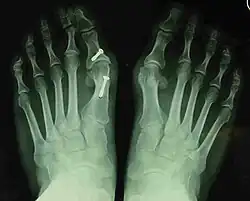

- Second metatarsal stress fracture (Fig. 5)

- Over-correction (Fig. 6)